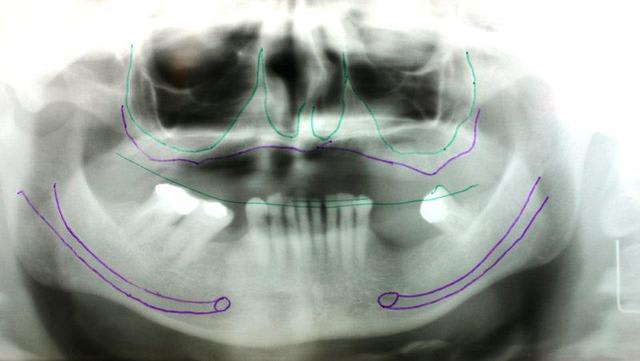

Le dentascan de la mandibule pour que vous compreniez mieux la difficulté...quais impossible de la considérer en cylindres même en déplaçant le NDI vous n avez aucune hauteur exploitable... Même des lame de Likow n y passent pas et les sous périostés sont interdits en Europe

J ai perdu mes deux foutus cylindres et ai dû les remplacer par deux double disk...et changer les deux mono disk du secteur droit

Et oui l implanto basale n est pas non plus un long fleuve tranquille